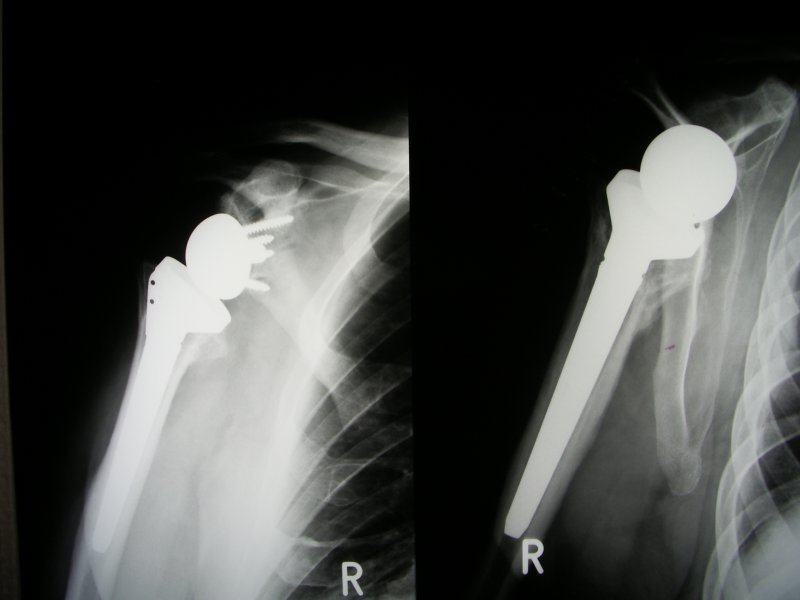

Zdjęcie tak zwanej "inverse" endoprotezy przy zerwanych przyczepach mieśni obręczy kończyny górnej / stożku rotatorów.

Zdjęcie endoprotezy po złamaniu pokazanym na powyższym zdjeciu